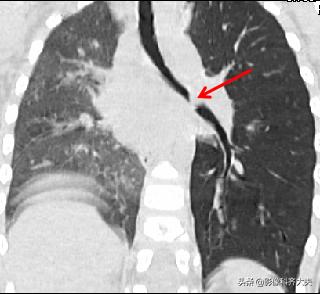

病例2、病史:患儿,男、1岁9个月,咳喘20天。家属否认异物吸入史。

图为正位普通X线片,显示左侧明显肺气肿改变,提示左侧支气管异物可能,因家属否认异物吸入,遂进一步做CT确诊。

CT冠状位重建明确显示左侧自气管阻塞,有明确异物的存在,红色箭头所示。